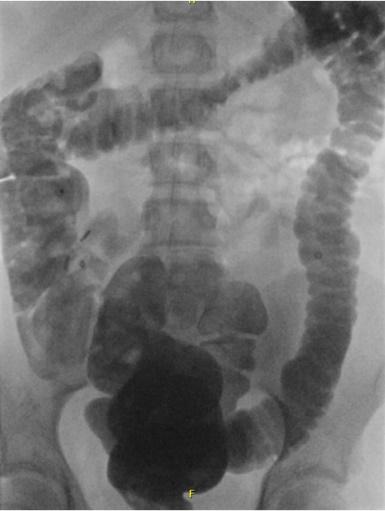

- Röntgenfoto van de buik: Hiermee kan worden bekeken hoe ernstig de verstopping is. Soms wordt dit gecombineerd met een markerstudie, waarbij uw kind capsules inneemt om de snelheid van de ontlasting te meten.

Coloninloop: Dit is een onderzoek waarbij contrastvloeistof via het poepgat wordt ingebracht om de dikke darm beter te bekijken. Daarna worden er een aantal röntgenfoto's na elkaar gemaakt, zodat de darm goed te zien is. Zo kan de arts goed beoordelen of de darm lang, wijd of kronkelig is.- Als uw kind dit spannend vindt, kan een medisch pedagogisch zorgverlener u en uw kind helpen om ervoor te zorgen dat dit proces zo soepel mogelijk verloopt.